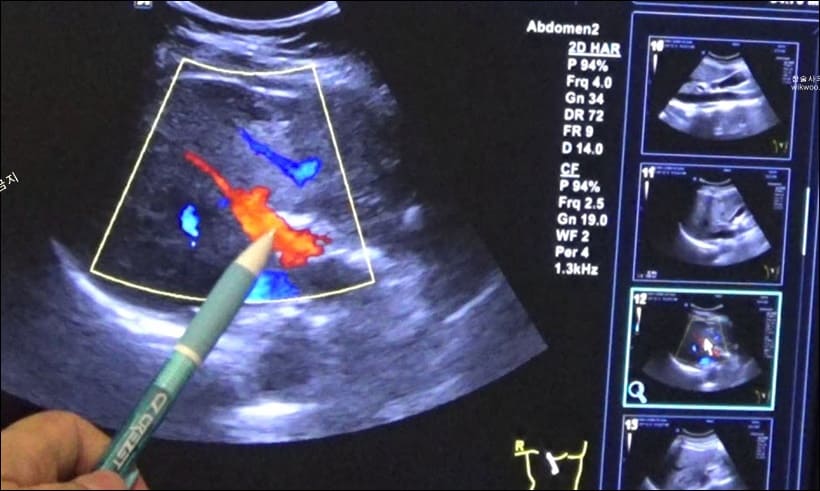

아래는 실제 사례인 후기들입니다.